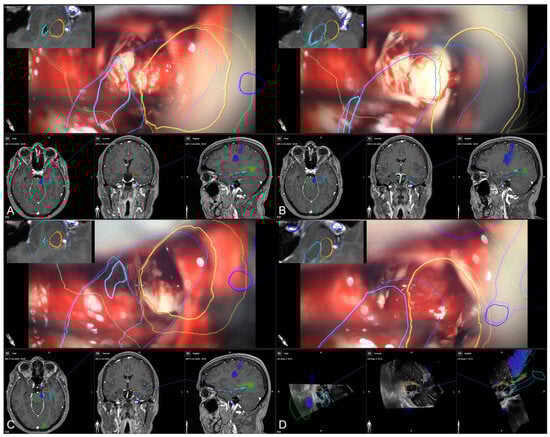

In the course of resection, image-guidance is provided on a screen close-by with the microscope’s focal point used as virtual pointer. In parallel, the outlines of all segmented structures (e.g., hippocampus, temporal horn, amygdala, brainstem) are visualized within the microscopic view, allowing for an immediate transfer of imaging data into the surgical situs (see Figure 7).

Figure 7. Microscope-based augmented reality and image-guidance in the course of surgery while assessing the temporal horn/hippocampus (A), the hippocampus (B), parts of the amygdala (C), and finally, showing the arachnoid level after resection of the amygdala (D) with preoperative MRI data (AC) as well as intraoperative US data after resection (D) in the navigation panel below the microscopic view in axial, coronal, and sagittal orientation, as well as a probe’s eye view (left upper corner) of preoperative MRI data according the recent microscope’s focal plane, allowing for immediate matching of imaging data and patient’s anatomy (blue: hippocampus, orange: amygdala, green: brainstem, light blue: temporal horn, dark blue: vessels).